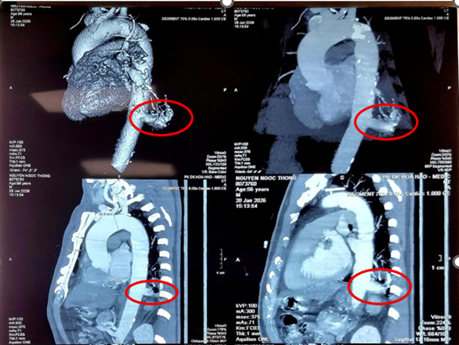

Phẫu thuật robot cắt phổi biệt lập, tránh nguy cơ tiềm tàng trong lồng ngực

Y học

Bệnh viện Bình Dân vừa thực hiện thành công trường hợp phẫu thuật robot cắt thùy dưới phổi trái điều trị bệnh lý phổi biệt lập nội thùy. Đây cũng là trường hợp phổi biệt lập được điều trị bằng phẫu thuật robot được báo cáo đầu tiên tại Việt Nam.